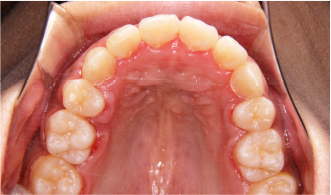

初診時、糸切り歯が上の方に生え、上下の側切歯(真ん中から2番目の歯)が中に入ってしまっている叢生の状態です。糸切り歯が他の歯より上に位置していることや歯が重なっていることで、磨き残しが多くなり、虫歯や歯肉炎、歯周病を誘発することになってしまいます。矯正治療を行うことで、見た目が改善されただけでなく、歯並びが整い、シンプルな歯磨きで清掃を行えるようになりました。歯並びを整えることは、管理しやすい環境をつくり、虫歯や歯肉炎から予防していくことに繋がるのです。

治療前、上下の歯並びのアーチが非常に狭いことで、歯が並びきらずにガタガタの歯並びになっている状態でした。このような狭い歯並びのことを歯科では「狭窄歯列(きょうさくしれつ)」といいます。特に下の歯並びのアーチが狭く、全体的に歯が内側に向かって倒れてしまっています。歯は横からの力に弱く、倒れている歯に噛む力が日々加わることで、過度な負担をかけてしまいます。

矯正治療で内側に倒れている歯を起こし、歯並びのアーチを広げることで、ガタガタの歯並びを改善しながら、噛む力に耐えられる構造に改善しました。